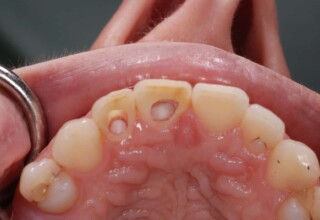

Composite Resin Veneers

Resin veneers are an inexpensive mode of esthetic improvement of anterior teeth, premolars also. Their potential is admirable and their limit is the operator’s clinical dexterity and imagination. In this case there were multiple problems with the upper four incisors: staining, poor inclinations, diastemas, multishading, poor interrelationship and poor tooth-gingiva ratios. They were restored with four direct composite resin veneers (one on a porcelain implant crown!) which were manufactured intraorally!!!